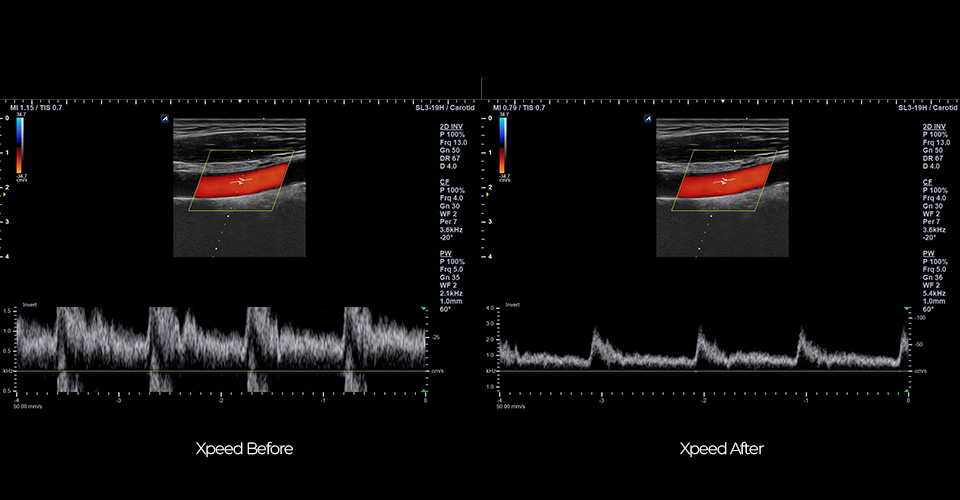

SL3-19H

X+ Crystal Signature™ linear transducer(3~19MHz)

Application:

MSK, Vascular, Small Parts, Breast, TCD, Abdomen, Pediatric, Gynecology, Obstetrics, EM